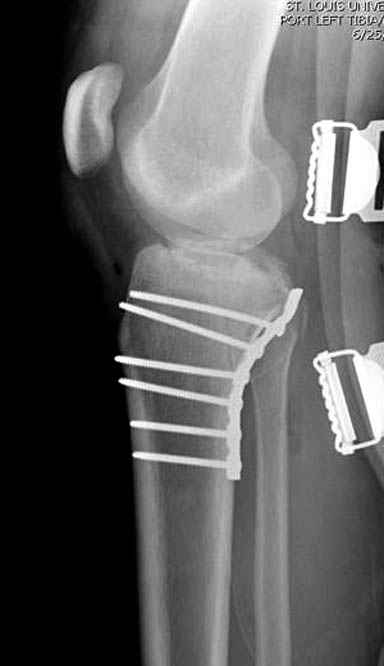

Трудно поверить, что разрекламированная Ортопедическая школа Восточной Украины позволяет такие странные снимки? На прямом снимке сохранен общий контур плато, но не известна судьба импрессии суставной поверхности. На полубоковой?, оставлен без репозиции задне-медиальный отдел, и навряд ли после такой фиксации можно удовлетвориться результатом.

Такая ситуация характерна для многих, когда принимается ошибочное решение, т.е пытаются фиксировать одним имплантом переломы двух мыщелков. Латеральная пластина приемлема только для тех случаев, когда сохраняется интактным медиальный диафизарный кортекс и отсутствует фрагментация на верхушке медиального перелома.

Если состояние мягких тканей позволяет, я бы предложил такой метод для вашего больного. Без предварительного планирования будет трудно, но шанс не надо упускать. Всего несколько дней после операции, и такая тактика лучше, чем недовольный молодой пациент.

Доступ к медиальной стороне задний или медиальный, через pes или в пространстве между medial gastroc мышцы.

Надеюсь, представленные снимки разных случаев помогут разобраться в тактике, и критика примется без личной обиды.